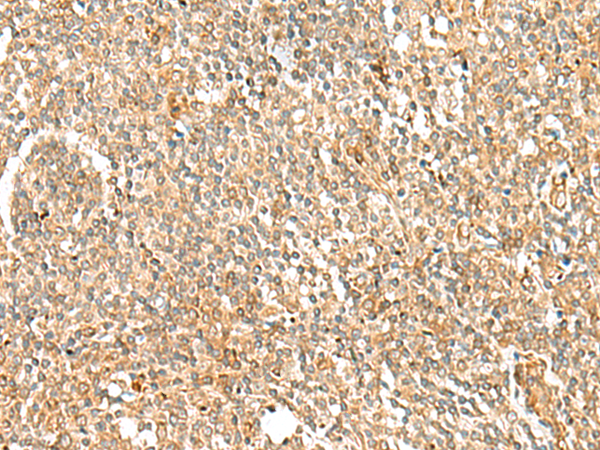

分类: 科研抗体货号: P02921别名: MADM; NRBP; BCON3; MUDPNP应用: WB,IHC反应种属: Human, Mouse